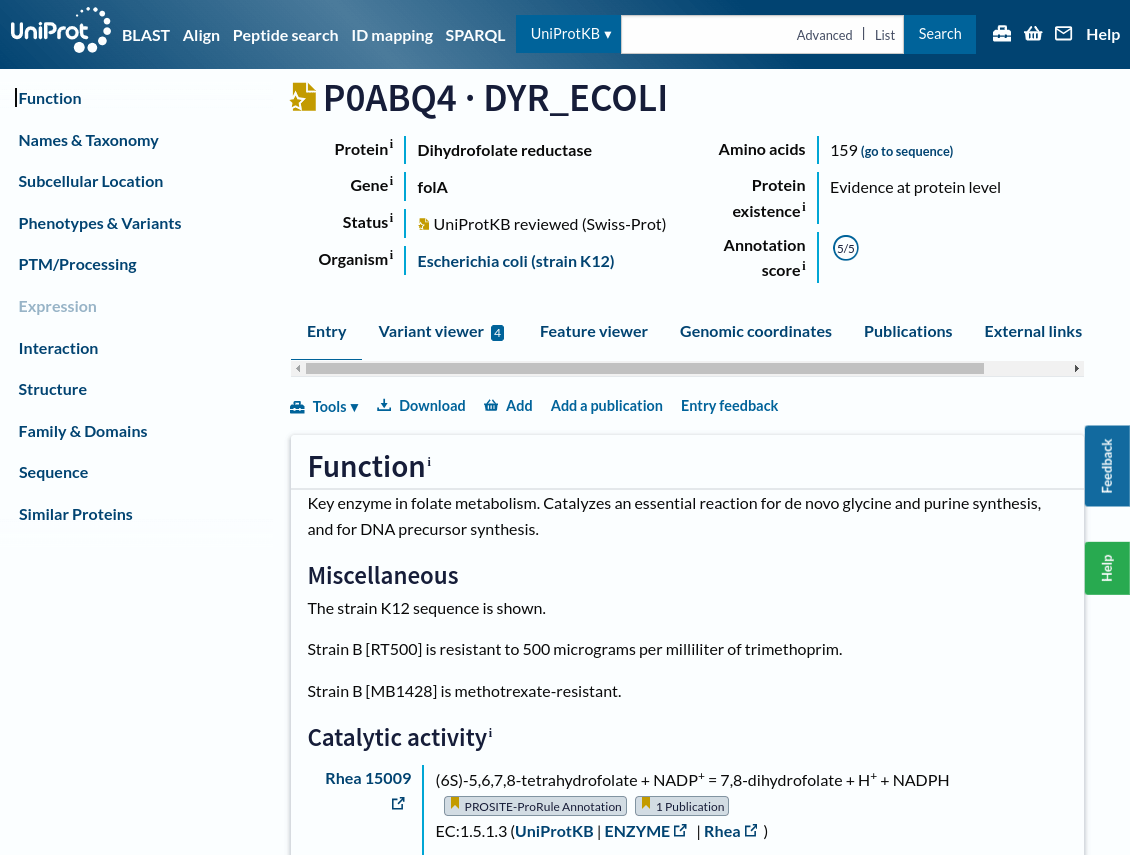

UniProt is a protein information database

Let's find information about our project's drug target: Dihydrofolate reductase

UniProt is a comprehensive database to access curated data about protein structures, functions, sequences, and annotations.

This page shows the results of a search in UniProtKB for a specific protein, in this case, "Dihydrofolate reductase"

On the left side, you have multiple filters to narrow your search results:

-

Reviewed (Swiss-Prot): Experts manually curated and verified these entries, ensuring high accuracy

-

Unreviewed (TrEMBL): These entries are automatically generated and have not been manually reviewed

Each row in the table represents a different protein entry

Entry ID: A unique identifier for the protein (e.g., P00383). You can click on this ID for detailed information about the protein

Protein Data Bank contains structures